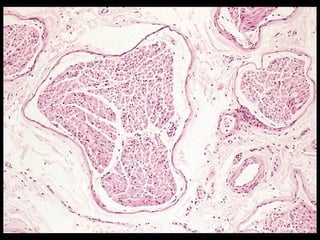

Meissner’s corpuscles

Encapsulated receptors

Contain Schwann cells that

form irregular, tortuous

lamellae

 Nerve fibers pass between

 Found in the papillary layer

of hairless skin (lips,

fingers, hands, foots)

 Respond to touch